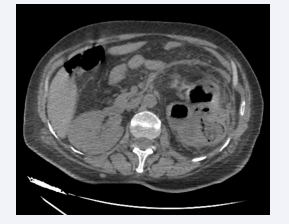

Axial section of an abdominal CT scan after intravenous  contrast injection at portal time showing an enlarged left kidney  with a nephrographic defect and surrounded by a posterior perirenal  collection containing air bubbles. The appearance is compatible with  class 3A EPN according to Huang et al.

Figure 1: Axial section of an abdominal CT scan after intravenous contrast injection at portal time showing an enlarged left kidney with a nephrographic defect and surrounded by a posterior perirenal collection containing air bubbles. The appearance is compatible with class 3A EPN according to Huang et al.